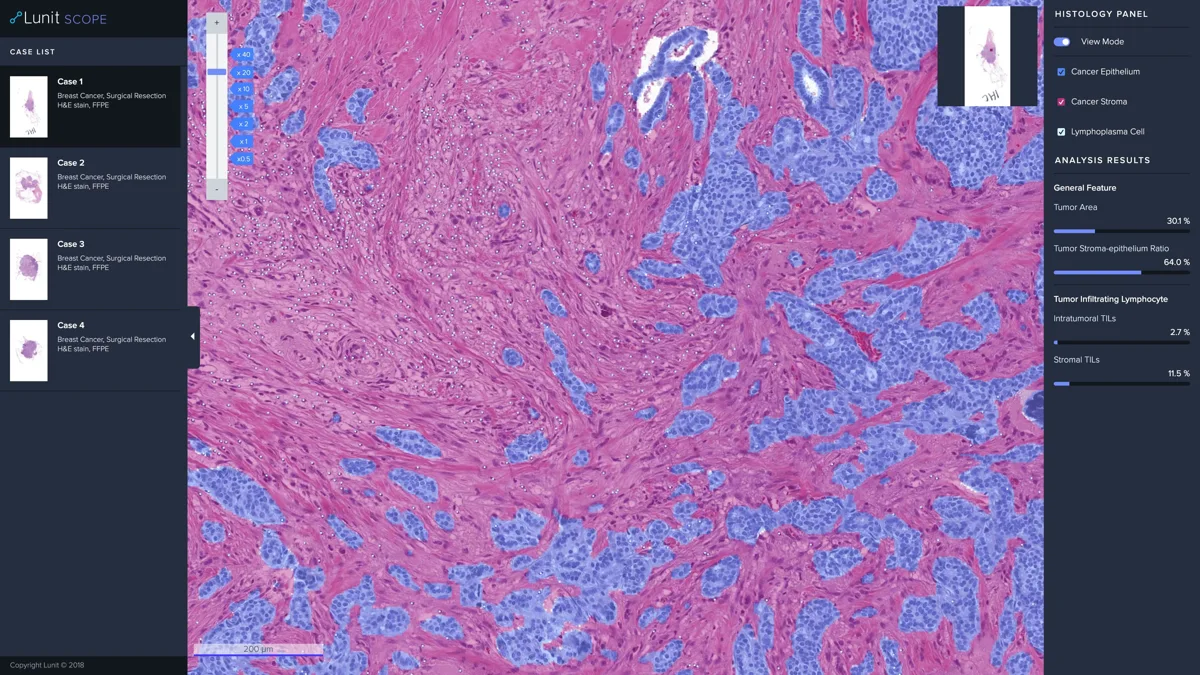

꾸준한 연구로 개발된 루닛의 인공지능 기반 조직 분석 플랫폼 ‘루닛 스코프 IO(Lunit SCOPE IO)’는 암의 치료 영역에서도 AI가 활용될 수 있음을 보여주고 있다. [상세내용 보기]

루닛 스코프 플랫폼은 환자의 조직 슬라이드 분석을 통해 암조직 종양침윤림프구(TIL) 분포를 세 가지 면역학적 형질로 분류(3-IP; 3 Immune Phenotypes), 각 형질에 따라 면역항암제 치료 예후가 달라진다는 점을 입증해왔다. 이는 세계 양대 암학회로 꼽히는 AACR 및 ASCO에서 발표돼 그 의미를 인정받은 바 있다.

이번 USCAP에서 발표하는 연구는 루닛 스코프 IO가 환자의 3-IP를 얼마나 높은 정확도로 분류할 수 있는지에 대한 병리과 전문의와의 비교 검증을 목표로 했다. 삼성서울병원, 분당서울대병원, 아주대병원의 병리학 연구팀과 데이터를 활용해 연구가 진행됐으며, 루닛 인공지능 플랫폼과 병리학 전문의의 분석 결과를 직접 비교했다.

비소세포폐암 환자의 조직 슬라이드를 3-IP로 분류한 결과, 병리학 전문의 집단은 평균 80.5%의 일치도를 보인 반면, 루닛 인공지능 플랫폼은 92.4%의 정확도로 3-IP 분류에 성공해 우수한 성능을 입증했다.  본 결과는 AI를 활용한 정확한 분류를 통해 환자의 항암치료 반응을 예측하고 보다 효과적인 맞춤형 치료를 제공할 수 있는 가능성을 의미한다.